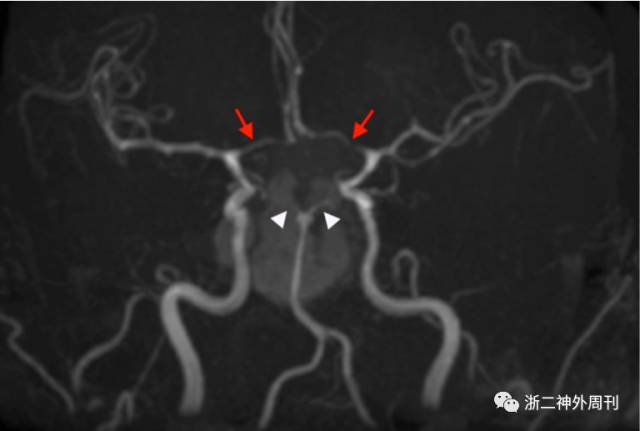

目前关于垂体卒中合并脑梗塞的形成机制,主要聚焦于机械压迫和血管痉挛两种学说上。机械压迫主要由于肿瘤卒中后在原有基础上快速增大,从而压迫了willis环上的血管继而产生脑梗塞。Zou回顾的36例病例中有19例发病原因为机械压迫,其中颈内动脉床突上段和海绵窦段最容易受累,大脑前动脉和中动脉其次,单侧更加容易受累[2]。而血管痉挛的发生一方面是由肿瘤出血后引起的蛛网膜下腔出血所致,另一方面由于卒中后的垂体瘤中大量坏死炎性组织释放后引起。既往文献中有许多病例报道通过MRA和CTA证实了血管痉挛的存在(图9)。当然,许多病例中存在两种因素的协同作用。

图9. 借助MRA可见痉挛的血管[8]。